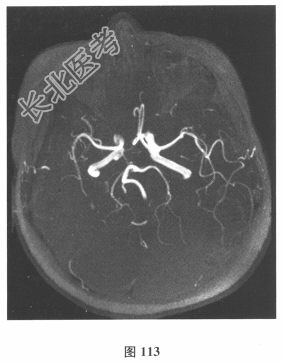

- 简答题2、脑脊液检查:常规、生化均正常,CSF-病毒TORCH(-),抗Hu、Yo、Ri均阴性,OB、MBP正常。血清抗Hu、Yo、Ri均阴性。颅脑MRI显示左颞枕、右顶枕多发长T₁、长T₂信号,Flair高信号,病变累及皮质及皮质下白质,病灶无强化,见图108~图114。)根据颅脑MRI,需要鉴别的疾病应是